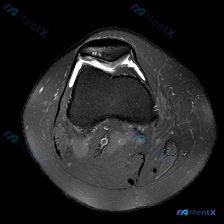

今天看到一份很有警示意义的膝关节MRI读片病例,整理出来和大家分享一下。这是一份经过髌股关节区域的膝关节轴位T2加权MRI,原始问题提示观察「软骨异常」,我们先把影像所见整理清楚:

- 髌股关节区域:髌骨前方及关节周围软组织可见弥漫性高信号,符合水肿/炎性渗出表现;髌股关节外侧间隙可见条带状高信号,提示大量关节积液;髌骨软骨下骨板表面轮廓不规则,水肿信号向髌骨前方软组织蔓延;股骨滑车软骨表面信号欠均匀。

- 股骨远端:骨皮质连续,髁形态基本完整,但关节周围软组织可见多处水肿高信号。

- 关节周围及腘窝:关节囊前侧、外侧可见液体积聚,髌前、外侧副韧带前方软组织广泛水肿;腘窝血管等后方结构形态正常,无明显占位。

核心影像总结:髌股关节软骨信号异常+大量关节积液+髌周广泛软组织水肿。